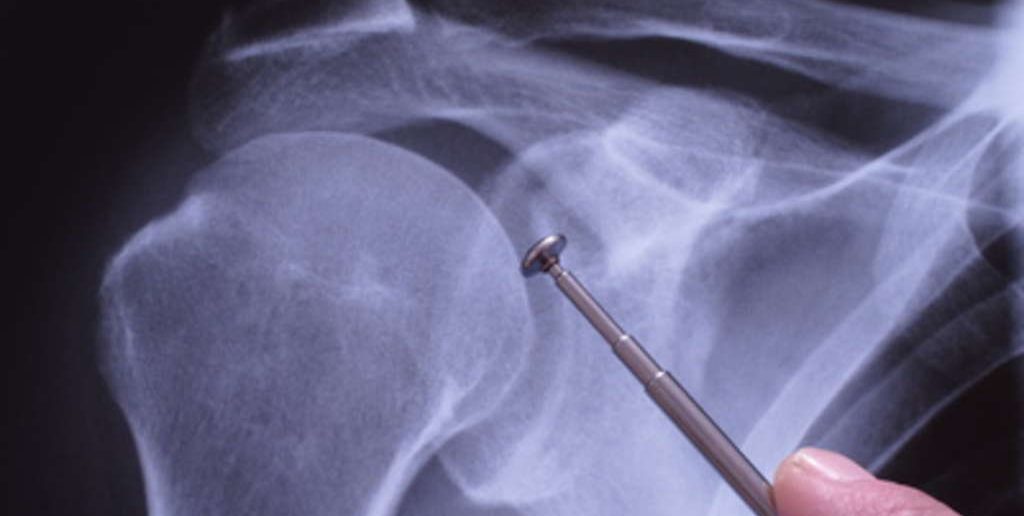

Sportverletzungen: Schulterprothese bei Arthrose und Fraktur – die Schulter-TEP

Verschieden Erkrankungen und Verletzungen können dazu führen, dass eine Schulterprothese nötig wird. Welche künstlichen Schultergelenke es gibt, wie sie funktionieren und wann sie eingesetzt werden, erklärt Björn Reindl in diesem Beitrag.

Die erste Schulter-Prothese wurde bereits in den 1950er Jahren von Charles Neer vorgestellt. Wie auch in der Forschung mit Hüft- und Knieprothesen gab es mehrere Entwicklungsschritte, und etwa seit den 1990er Jahren ist eine 3. Generation der Schulter-Endoprothesen im Umlauf.

In Deutschland werden etwa 3000 künstliche Schultergelenke eingebaut. Vergleicht man das mit der Zahl der künstlichen Hüftgelenke (ca. 150.000 ) oder der der Knieprothesen (100.000 ) ist das noch verhältnismäßig wenig. Die Tendenz ist allerdings stark steigend, auch bei Sportverletzungen.